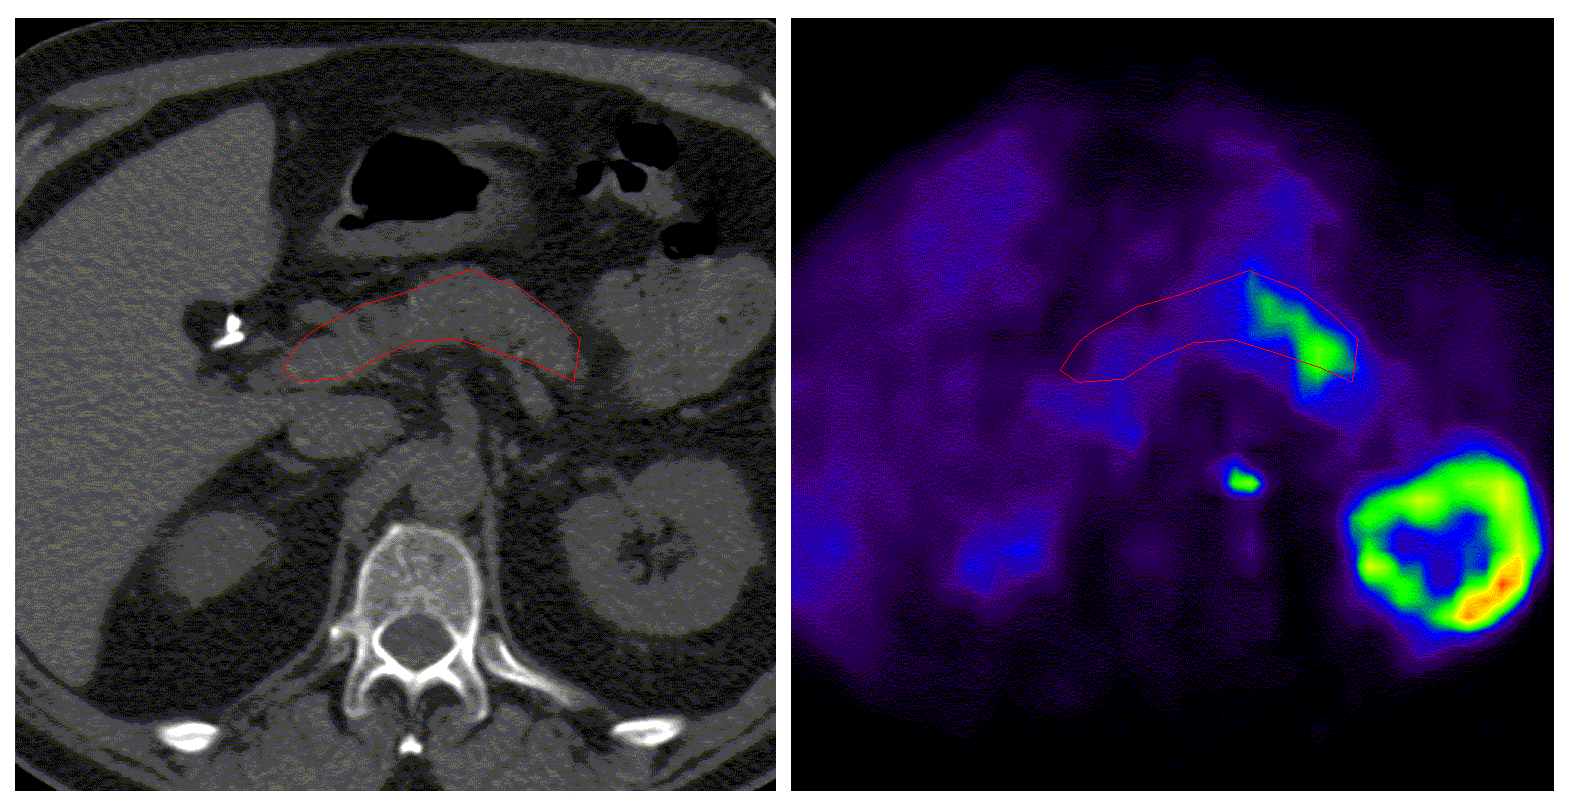

1. Draw ROIs on pancreas and calculate tissue TACs. See Figure 1. Make sure that TAC data files do not contain aortic TACs!

Example of pancreas ROI

Figure 1. Example of pancreas ROI.